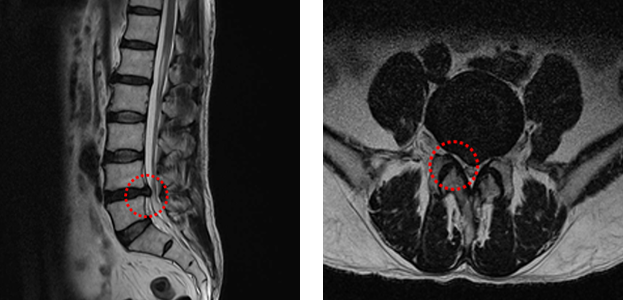

Normal Patient MRI

• Lateral View MRI

• Cross-sectional MRI

Disc Herniation MRI